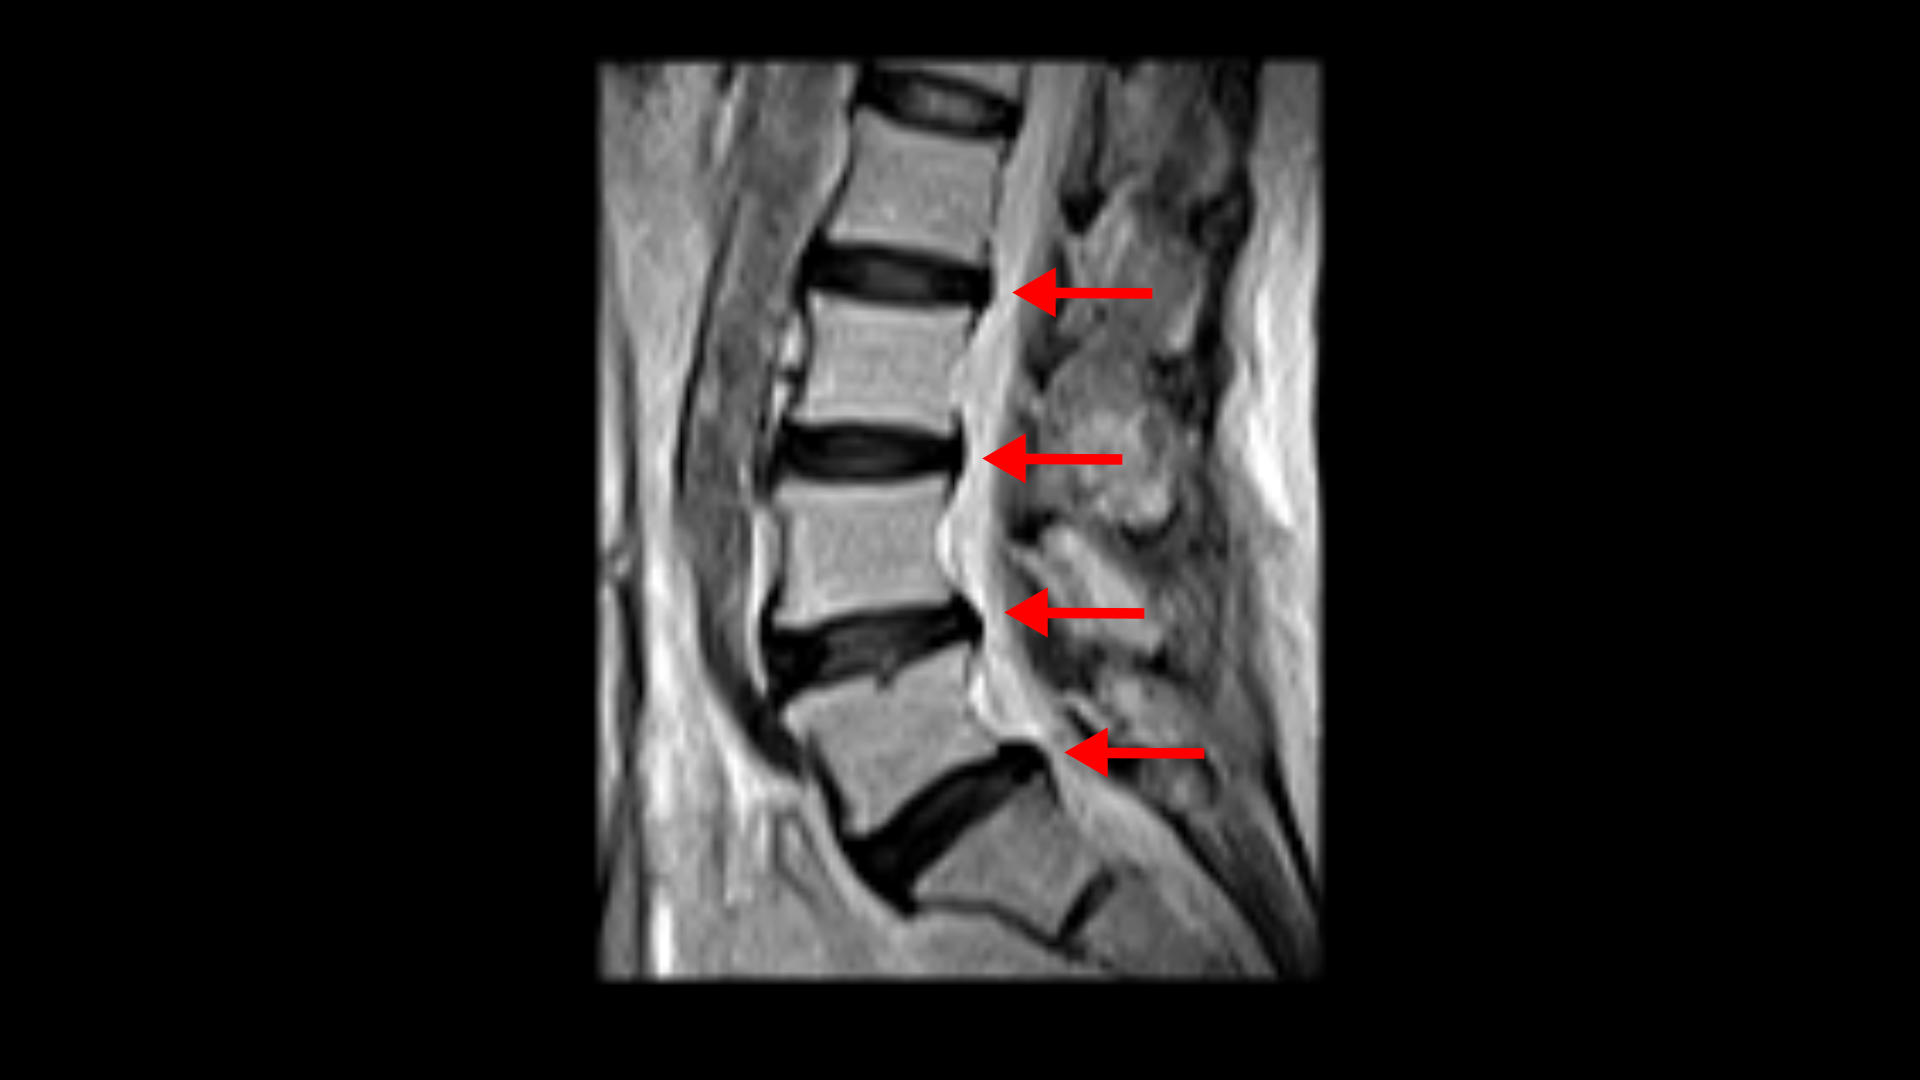

우선 이 환자분의 X-ray를 보면 5번 1번에 전방전위증으로 인한 불안정성이 있습니다. 척추가 불안정하므로 전방전위로 뼈가 밀려 나간 정도가 MRI에 보이는 것보다 X-ray 굴곡상태에서 보는 게 훨씬 더 심해 보입니다. 또 척추 여러 마디에 퇴행성 병변이 보입니다.

그리고 허리 4마디에 퇴행성 허리디스크가 있습니다.